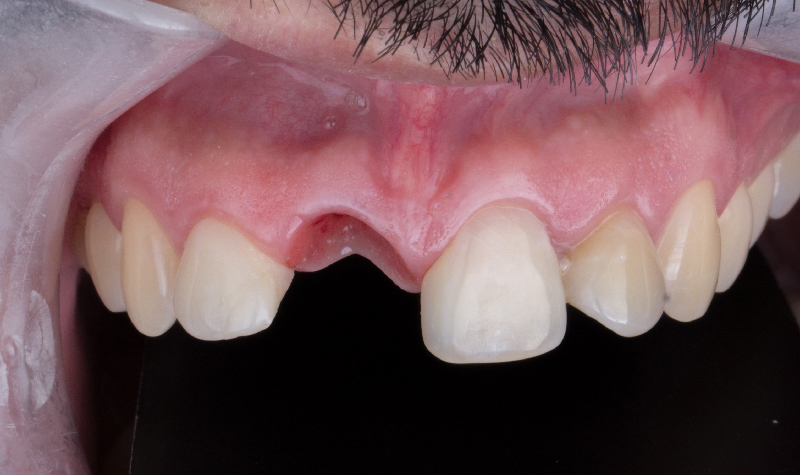

Rehabilitación oral total con prótesis inferior sobre implantes y coronas superiores.

Prótesis híbrida inferior de cerámica fija sobre implantes.